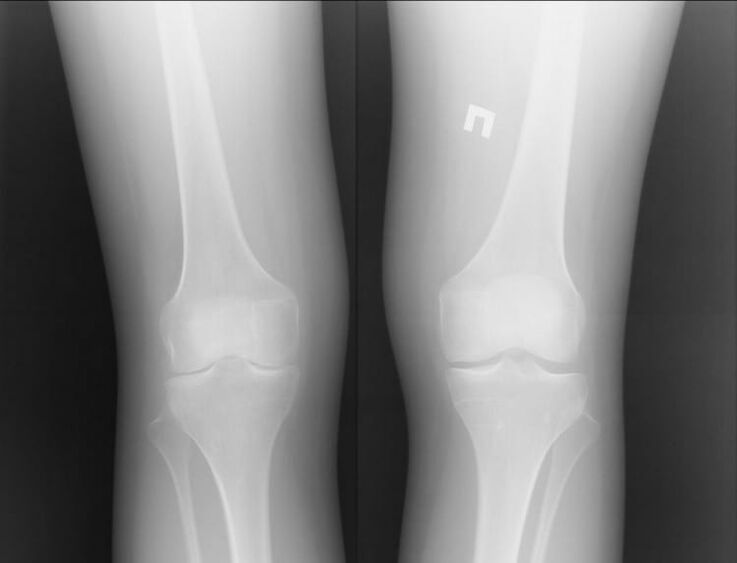

Obě tyto nemoci jsou přirozeně docela závažné a je těžké říci, která z nich je horší. Můžeme však zvážit příklad problému v kolenním kloubu. U artritidy to znamená, že se zánětlivými procesy může být pacientovi pomoci.

Nejčastěji k tomu dochází v důsledku jiných infekcí, které se vyskytují v lidském těle. Pokud jsou vyléčeny a zánět kloubu je odstraněn, pak vás artritida kolena už nebude obtěžovat.

Artróza je úplně jiný příběh. Jedná se o nezávislé onemocnění způsobené problémy v tkáni chrupavky. To často nelze provést bez chirurgického zásahu. Poté následuje další dlouhý proces obnovy.

Můžeme proto říci, že artróza je vážnější onemocnění. Artritida však může způsobit první onemocnění. Obě nemoci by neměly být zanedbávány. Je lepší okamžitě kontaktovat specialistu.